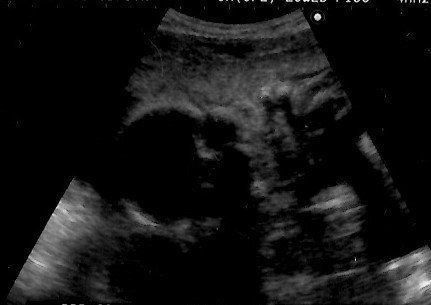

妊娠12週目のエコー写真 つわりもなく、快適なマタニティーライフを満喫

ラッキーなことに、妊娠中の私はいわゆる“つわり”の症状はなく、体調も安定していました。おかげで会社にもそれまで通り出勤していました。また妊娠中は味覚が変わるとも聞くのですが、私はそうしたことも全くナシ。さすがにアルコールは断っていたものの、「出産したらなかなか外食もできないから」を言い訳に、友人との食事会にもどんどん参加していました。